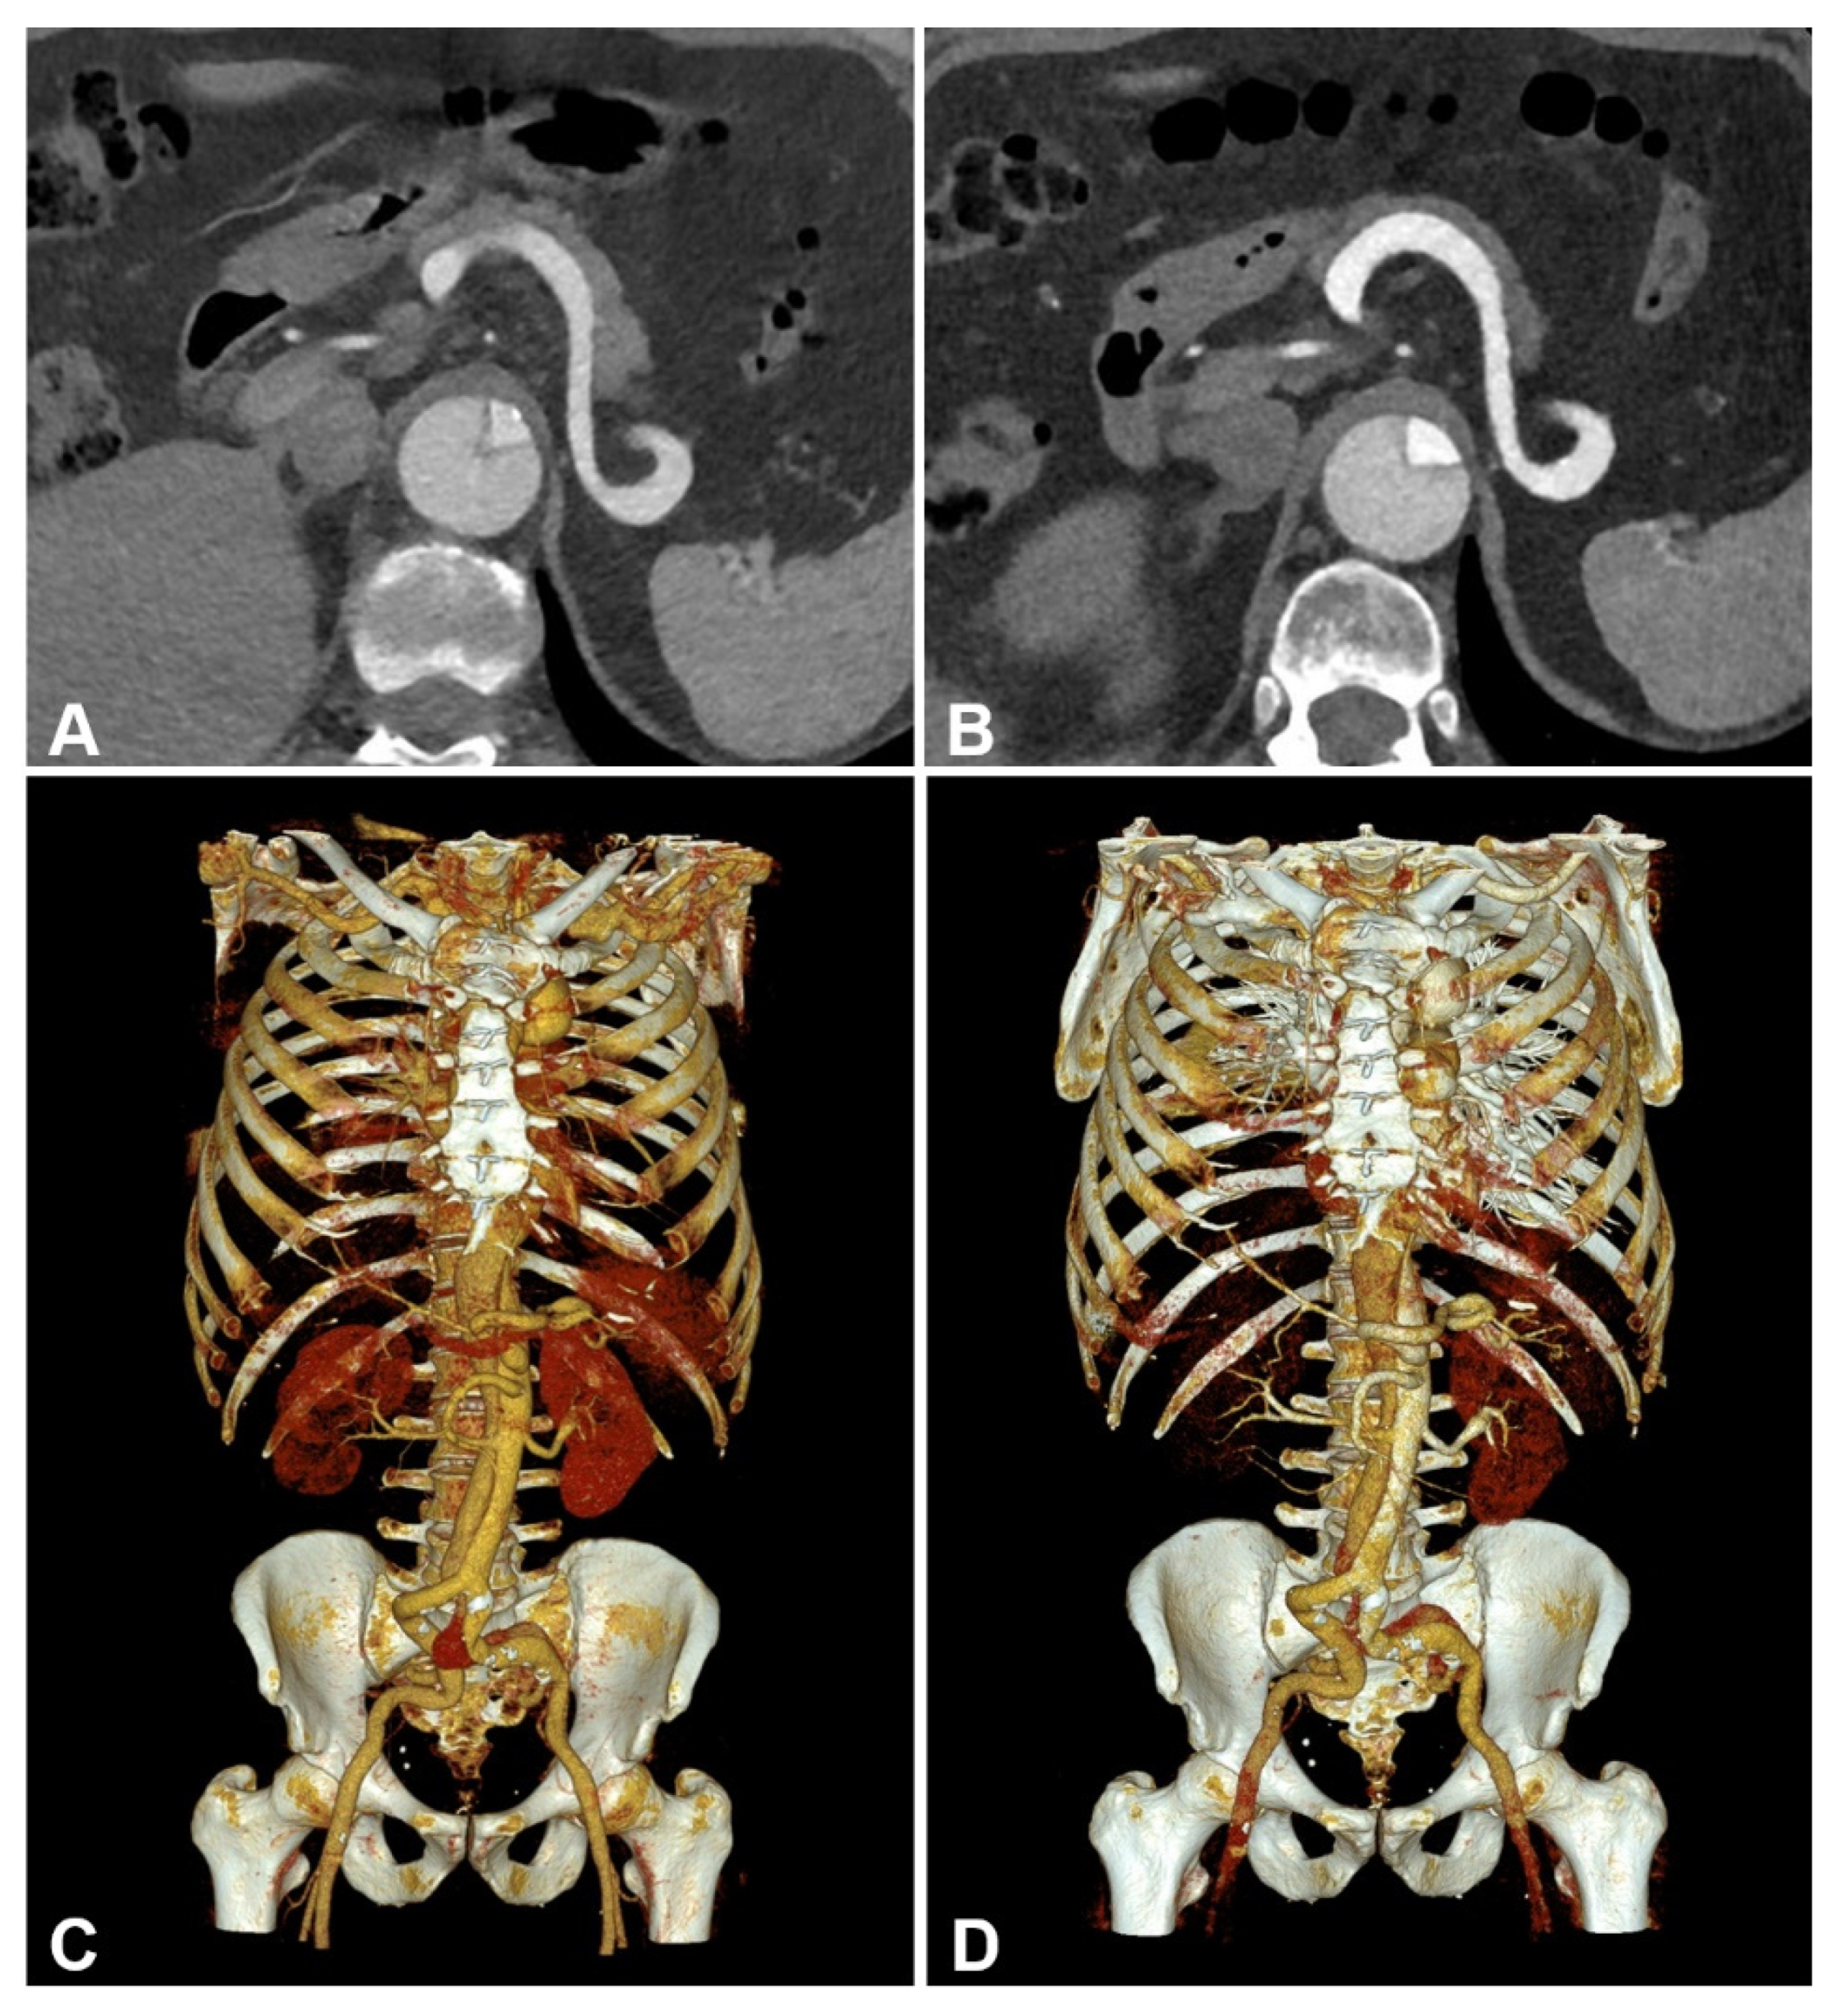

An Intra-Individual Comparison of Low-keV Photon-Counting CT versus Energy-Integrating-Detector CT Angiography of the Aorta

- Higashigaito, K.; Mergen, V.; Eberhard, M.; Jungblut, L.; Hebeisen, M.; Rätzer, S.; Zanini, B.; Kobe, A.; Martini, K.; Euler, A.; et al. CT Angiography of the Aorta Using Photon-counting Detector CT with Reduced Contrast Media Volume. Radiol. Cardiothorac. Imaging 2023, 5, e220140. [Google Scholar] [CrossRef] [PubMed]

- Euler, A.; Higashigaito, K.; Mergen, V.; Sartoretti, T.; Zanini, B.; Schmidt, B.; Flohr, T.G.; Ulzheimer, S.; Eberhard, M.; Alkadhi, H. High-Pitch Photon-Counting Detector Computed Tomography Angiography of the Aorta: Intraindividual Comparison to Energy-Integrating Detector Computed Tomography at Equal Radiation Dose. Investig. Radiol. 2022, 57, 115–121. [Google Scholar] [CrossRef]